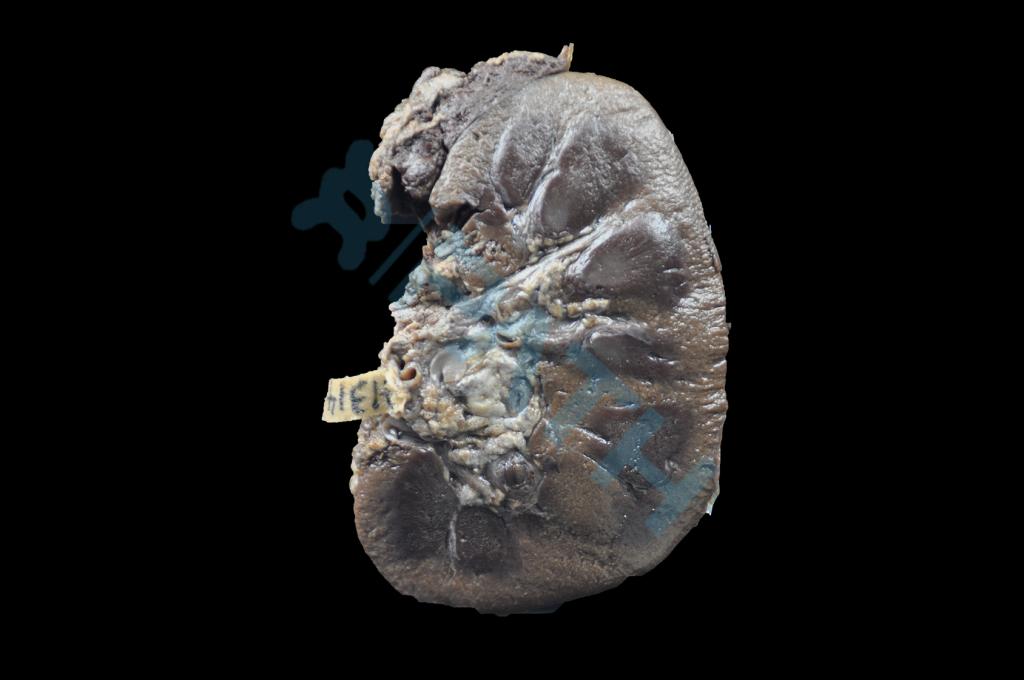

泌尿系统疾病